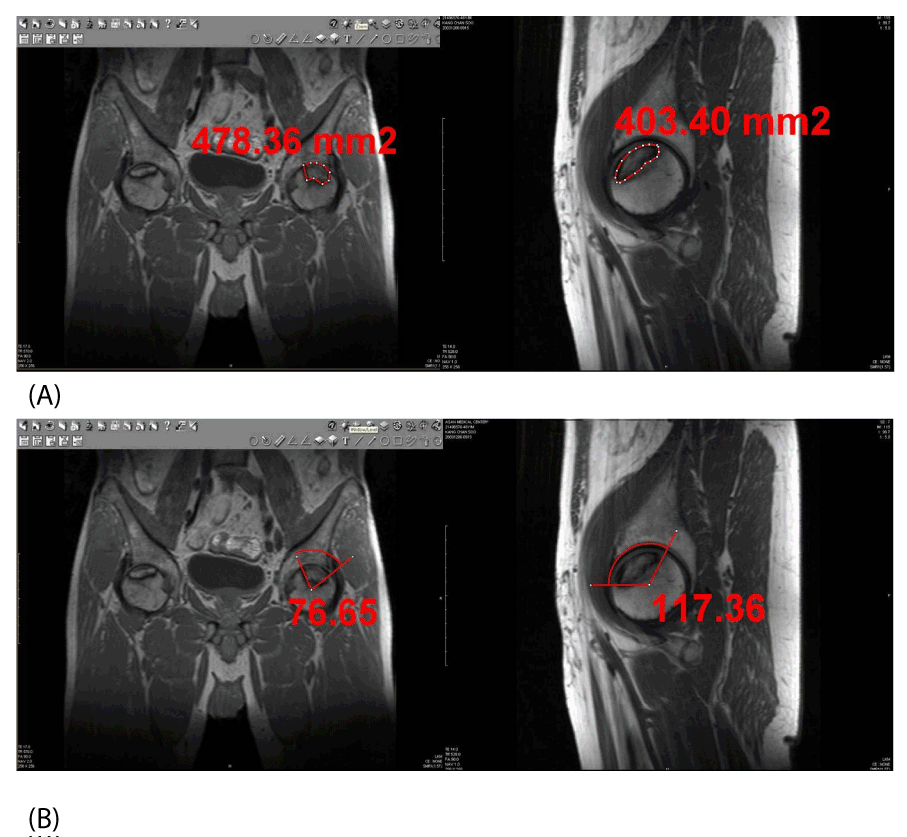

| Figure 1: 48-year-old male with osteonecrosis of the both femoral heads. To check amount of osteonecrosis we evaluated T1-weighted coronal and sagittal MR image. (A) Absolute value of the osteonecrosis was evaluated by the tool measuring size in the PACS. (B) Necrotic angle of the osteonecrosis was evaluated by the tool measuring angle in the PACS. |